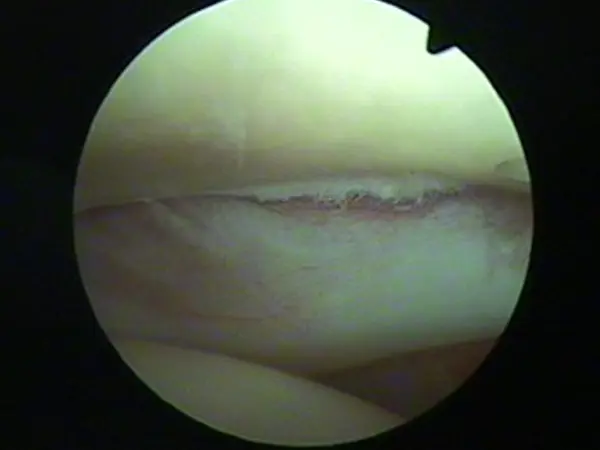

Ortopædi

Skovshoved dyreklinik har special kompetence indenfor ortopædi og fungerer som henvisningsklinik for patienter med ortopædiske lidelser.